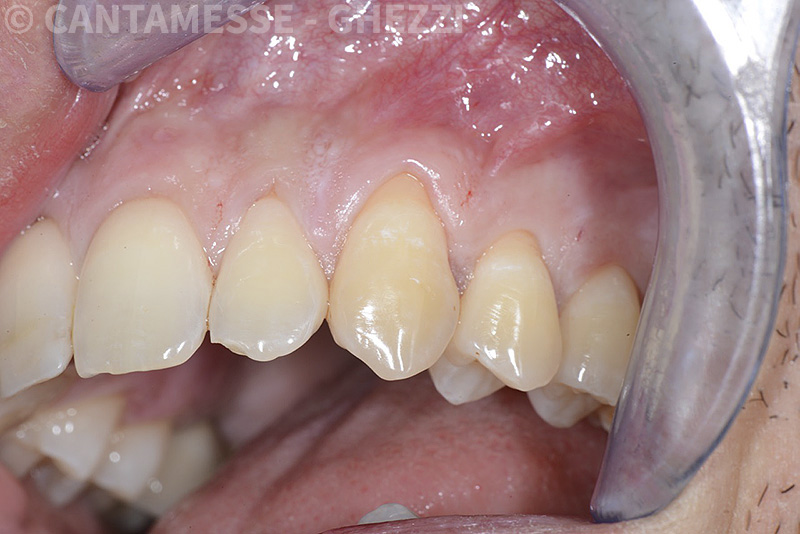

PREMESSA: in seguito all’estrazione dell’incisivo laterale superiore di destra, resasi necessaria per cause batteriche, si decide di affrontare il caso con il posizionamento di un impianto in sostituzione dell’elemento mancante dopo guarigione del sito infetto. Con tecniche rigenerative sia dei tessuti ossei mancanti a causa dell’infezione pregressa, sia dei tessuti gengivali che appaiono inizialmente troppo spostati in alto, si ripristina una corretta morfologia delle parabole (contorni) gengivali e delle papille interdentali (triangoli di gengiva tra due denti vicini).

Vengono utilizzati 2 tipi di provvisori: il primo, cementato ai denti vicini, viene utilizzato dal momento dell’estrazione del dente fino ad impianto osteointegrato (circa 6 mesi); il secondo, avvitato direttamente all’impianto, ha una funzione di prova estetica ma soprattutto di guida per la maturazione dei tessuti gengivali peri-implantari portandoli verso la maturazione completa prima di posizionare la corona finale in disilicato di litio.